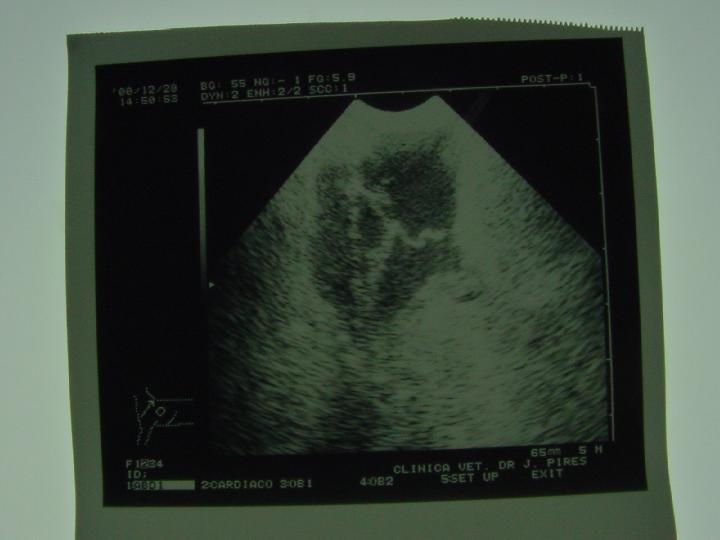

Ecografia: É o exame da escolha no diagnóstico das afecção prostáticas.A ecografia revela um aumento do parênquima prostático.

Ecografia – É o exame de escolha nas afecções prostáticas. A ecografia revelou a presença de um quisto único de grande dimensão. A ecografia permite visualizar uma massa anechogénica.